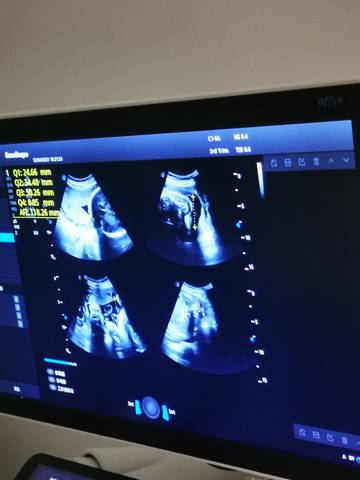

亲爱的,我看的图片孩子发育的也还不错的呀,正常来说的话应该没有什么问题的话,你自己多注意补充营养吧。